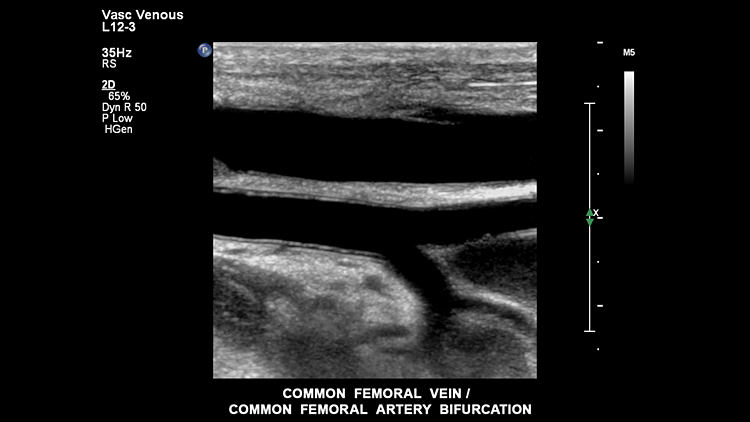

Общая бедренная вена, общие бифуркации бедренной артерии, L12-3